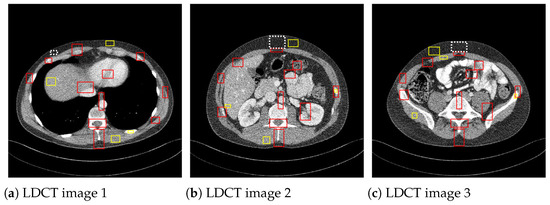

Moreover, to show the denoising performance of the proposed method on low-dose CT images, we used different noisy low dose (quarter-dose exposure images) abdominal CT images (Figure 4) from the 2016 NIH-AAPM-Mayo Clinic Low Dose CT Grand Challenge [30].

Figure 4. Low-dose (quarter-dose) abdominal CT medical images, 512 × 512 pixels.

where x i j , η i j , y i j are the pixels of the original, the noisy, and the denoised image, respectively. To analyze the filtering efficiency in the case of the noisy low dose CT images, where there is no noise-free reference image, the image quality metrics used were the signal-to-noise ratio (SNR) [34], the contrast-to-noise ratio (CNR) [34], and the average equivalent number of looks (ENL) [34]. The CNR measures the contrast between an image feature and an area of homogeneous noise, while the ENL measures smoothness in areas that should have a homogeneous appearance but are corrupted by noise. These image quality metrics are defined as:

where I is the matrix of pixel values for the CT image, and σ n 2 is the noise variance computed on a homogeneous region. μ m is the mean of the pixels in the mth region of interest (ROI), σ m is standard deviation, and μ b and σ b are the pixel mean and standard deviation of a homogeneous region of the image, respectively. The CNR values are averaged over the red ROIs shown in Figure 5 and the ENL over the yellow homogeneous ROIs. To compute σ b 2 , the homogenous ROI in Figure 5, delimited by a dashed line, was used.

Figure 5. ROIs considered to compute CNR and ENL measures.